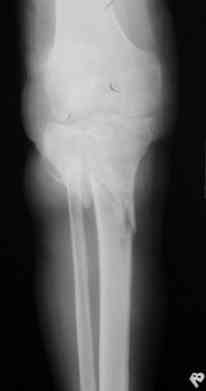

Р-граммы за март и апрель